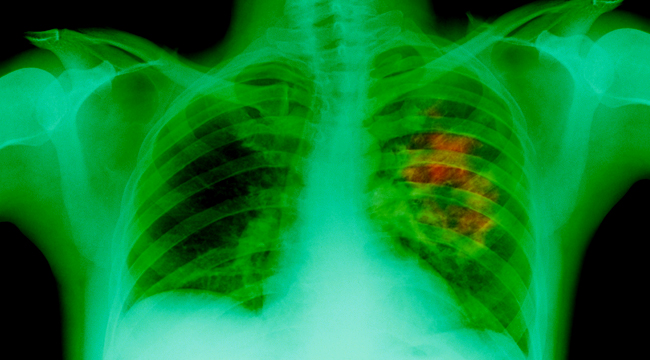

In October 2016, the man found himself short of breath for three weeks despite the lack of symptoms of a cough. He went to his primary care provider, who took X-ray and CT scans of his lungs.

The scans found a tumorous mass in his left lung. A follow-up test confirmed that he had lung adenocarcinoma and mediastinal lymph nodes.

New X-ray scans of his lungs revealed that the tumors in his lung shrunk by 50 percent. Furthermore, his lung cancer reversed its progress.